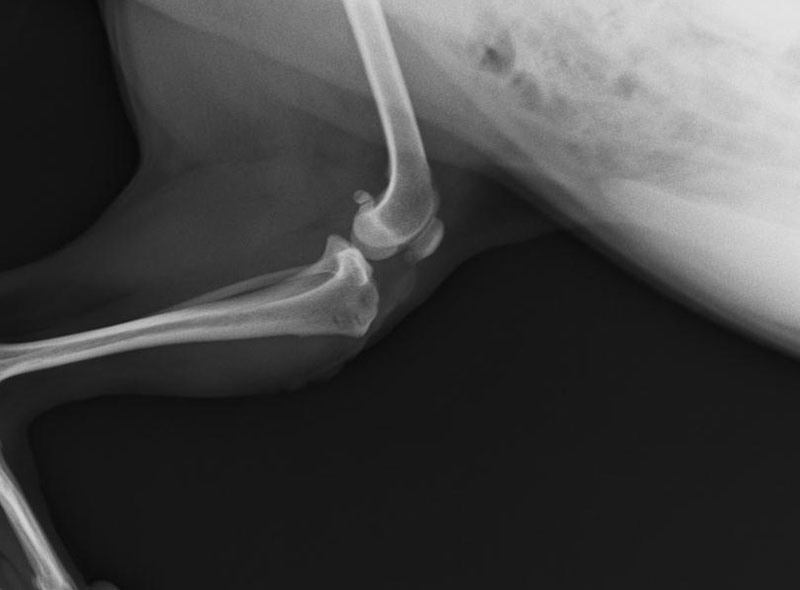

前十字靭帯断裂

前十字靭帯は、大腿骨と下腿骨(脛骨)が前後にずれない様につなぎ止めている靭帯です。

この靭帯が、激しい運動や踏み外しなどにより、ちぎれてしまうと、足を上げっぱなし、または上げ気味に使います。

完全断裂の場合は、靭帯を再建する手術が必要となります。

-

前十字靭帯完全断裂 手術前

前十字靭帯完全断裂 手術後